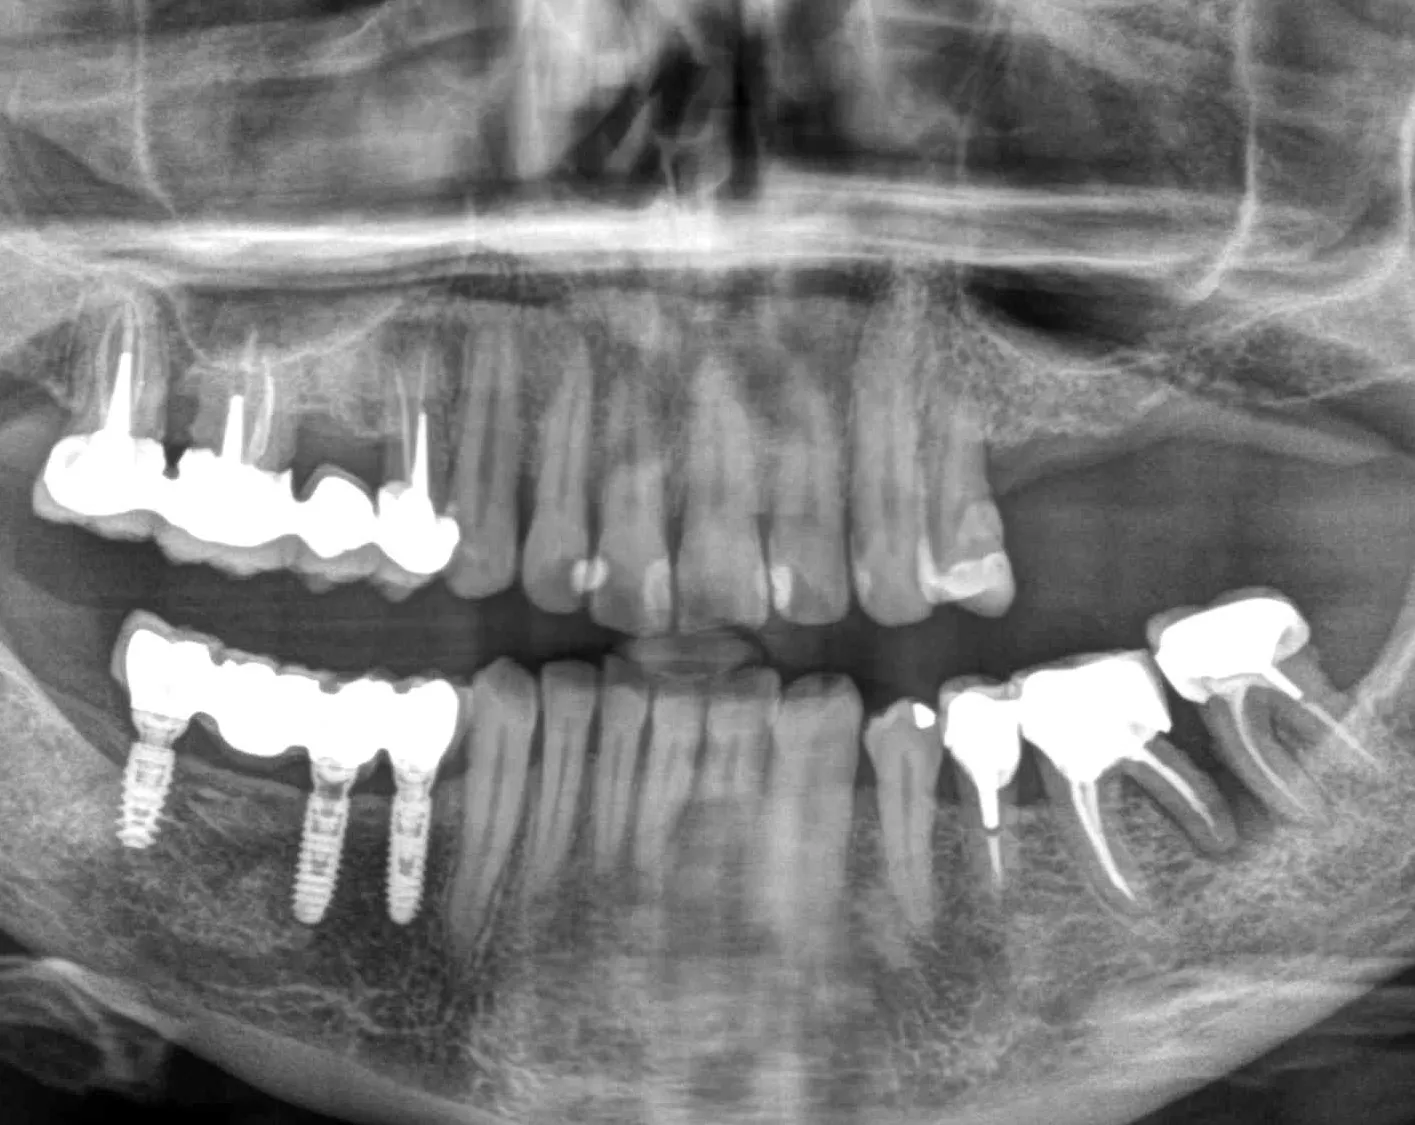

A 60-year-old female patient presented at our office. She was in good health and a non-smoker, and had healthy periodontal tissue and good oral hygiene. Teeth 25, 26, and 27 had been missing for several years, and there was insufficient bone to place implants. However, quadrant four had been the priority, with 3 Axiom® REG implants being placed there in 2019. An inspection of quadrant three revealed significant damage to 36 and misalignment of 37.

Therefore, we opted for a shortened dental arch that would replace 25 and 26 but not 27. We decided to perform simultaneous sinus floor augmentation and implant placement, as there was only 4 mm of native bone at the implant sites.

1-2. Panoramic radiography and cone-beam computed tomography showing vertical bone loss. With only 4 mm of sinus floor bone, implant placement was not feasible.